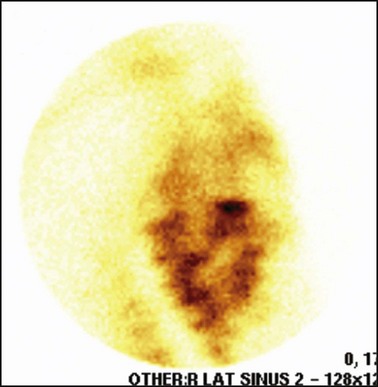

99mTc-MDP uptake associated with periapical infection is typically focal and intense, with IRU located over the apical region of the affected tooth (Fig. 13.48). Region of interest (ROI) studies performed on cases of periapical infection have shown IRU of 24–259 % greater than the same region on the contralateral side when using right and left lateral views.14,25 Because ‘strike through’ (lesions with high uptake may emit gamma rays from the contralateral side of the skull) may occur when comparing two lateral views, ROI taken from left and right sides on a dorsal (or ventral) view can show an even greater IRU % (as high as 700 %14) on the affected side compared with the control side. If periapical infection is accompanied by secondary dental sinusitis, the focal intense uptake over the affected apex is surrounded by a diffuse region of moderately increased activity over the affected sinus(es) (Fig. 13.48B). After dental extraction, areas of IRU can be present for up to 24 months postoperatively (Fig. 13.49), presumably due to continued remodeling of the dental alveolus.14

image image

Fig. 13.48 Scintigrams of two horses with periapical infection of (A) 108 lateral and dorsoventral views and (B) 209 (this horse has concurrent sinusitis).

Horses with primary sinusitis may show variable patterns of IRU within the affected paranasal sinuses, but generally IRU is more diffuse and less marked (6–300 %)14,25 than is seen with periapical infection. It should be possible to identify the rostral and caudal maxillary and frontal sinuses individually on scintigrams based on anatomical location with respect to the cheek teeth and ethmoturbinates.

Some cases of equine primary sinusitis exhibit focal area(s) of moderate to marked IRU (26–320 % increase compared with contralateral side;14 Fig. 13.50). This is an important finding, because if these focal areas of IRU that are observed in cases of primary sinusitis happen to be positioned over the apex of a cheek tooth, a false diagnosis of periapical infection may be made. Careful, three-dimensional localization of the focal area of IRU may help prevent such false diagnoses in some cases.